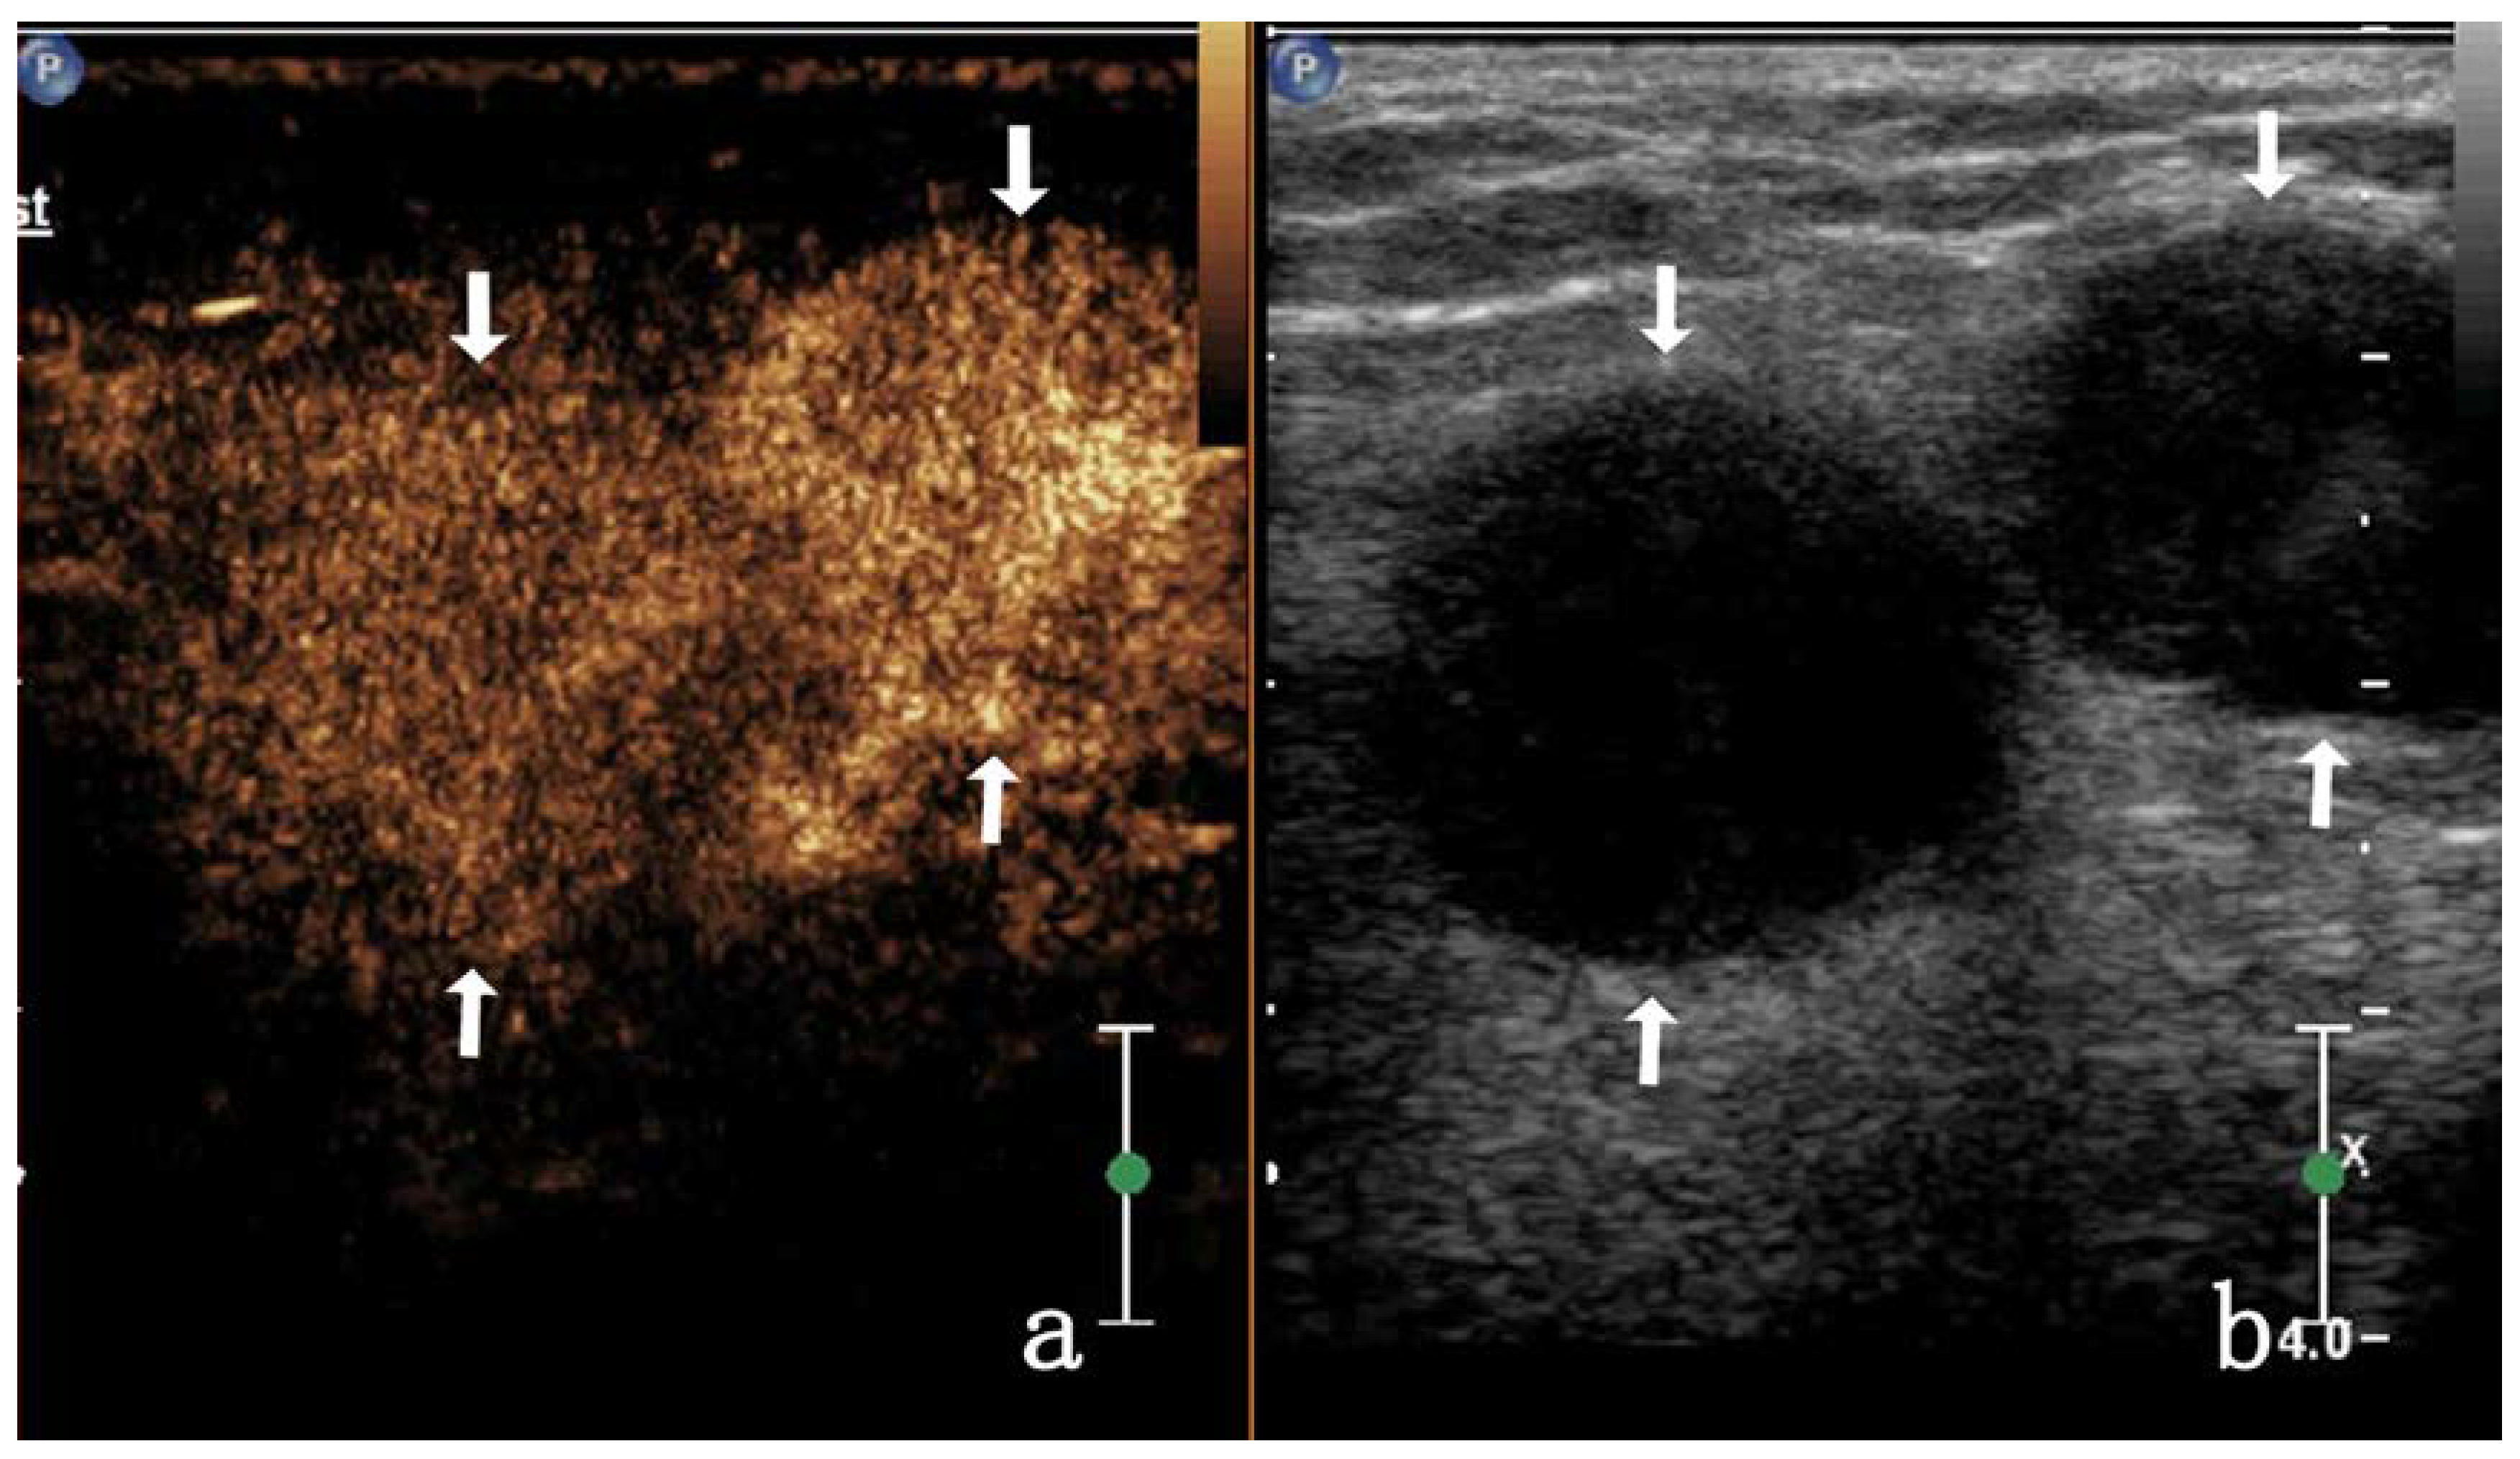

| CEUS degree | 18.865 | 0.000 | |||

| Homogeneous enhancement | 3/17 (17.64%) | 23/28 (82.14%) | |||

| Heterogeneous enhancement | septal enhancement | 4/17 (23.52%) | 0 | ||

| Annular enhancement | 4/17 (23.52%) | 5/28 (17.85%) | |||

| Nodule-in-nodule enhancement | 3/17 (17.64%) | 0 | |||

| non-enhancement | 3/17 (17.64%) | 0 | |||

| Enhanced intensity | 17.455 | 0.000 | |||

| Low enhancement | 5/17 (29.41%) | 0 | |||

| Equal enhancement | 4/17 (23.52%) | 0 | |||

| High enhancement | 8/17 (47.05%) | 28/28 (100%) | |||

| CEUS mode | 15.074 | 0.000 | |||

| Centripetal enhancement | 0 | 16/28 (57.14%) | |||

| Noncentripetal enhancement | 17/17 (100%) | 12/28 (42.85%) | |||